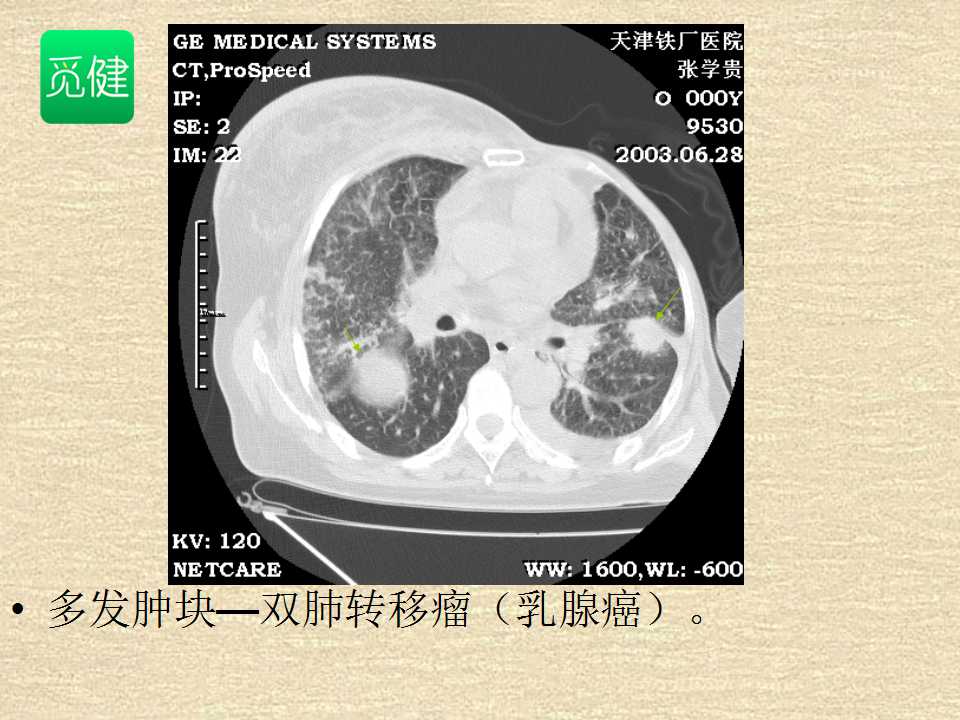

肺癌影像学表现